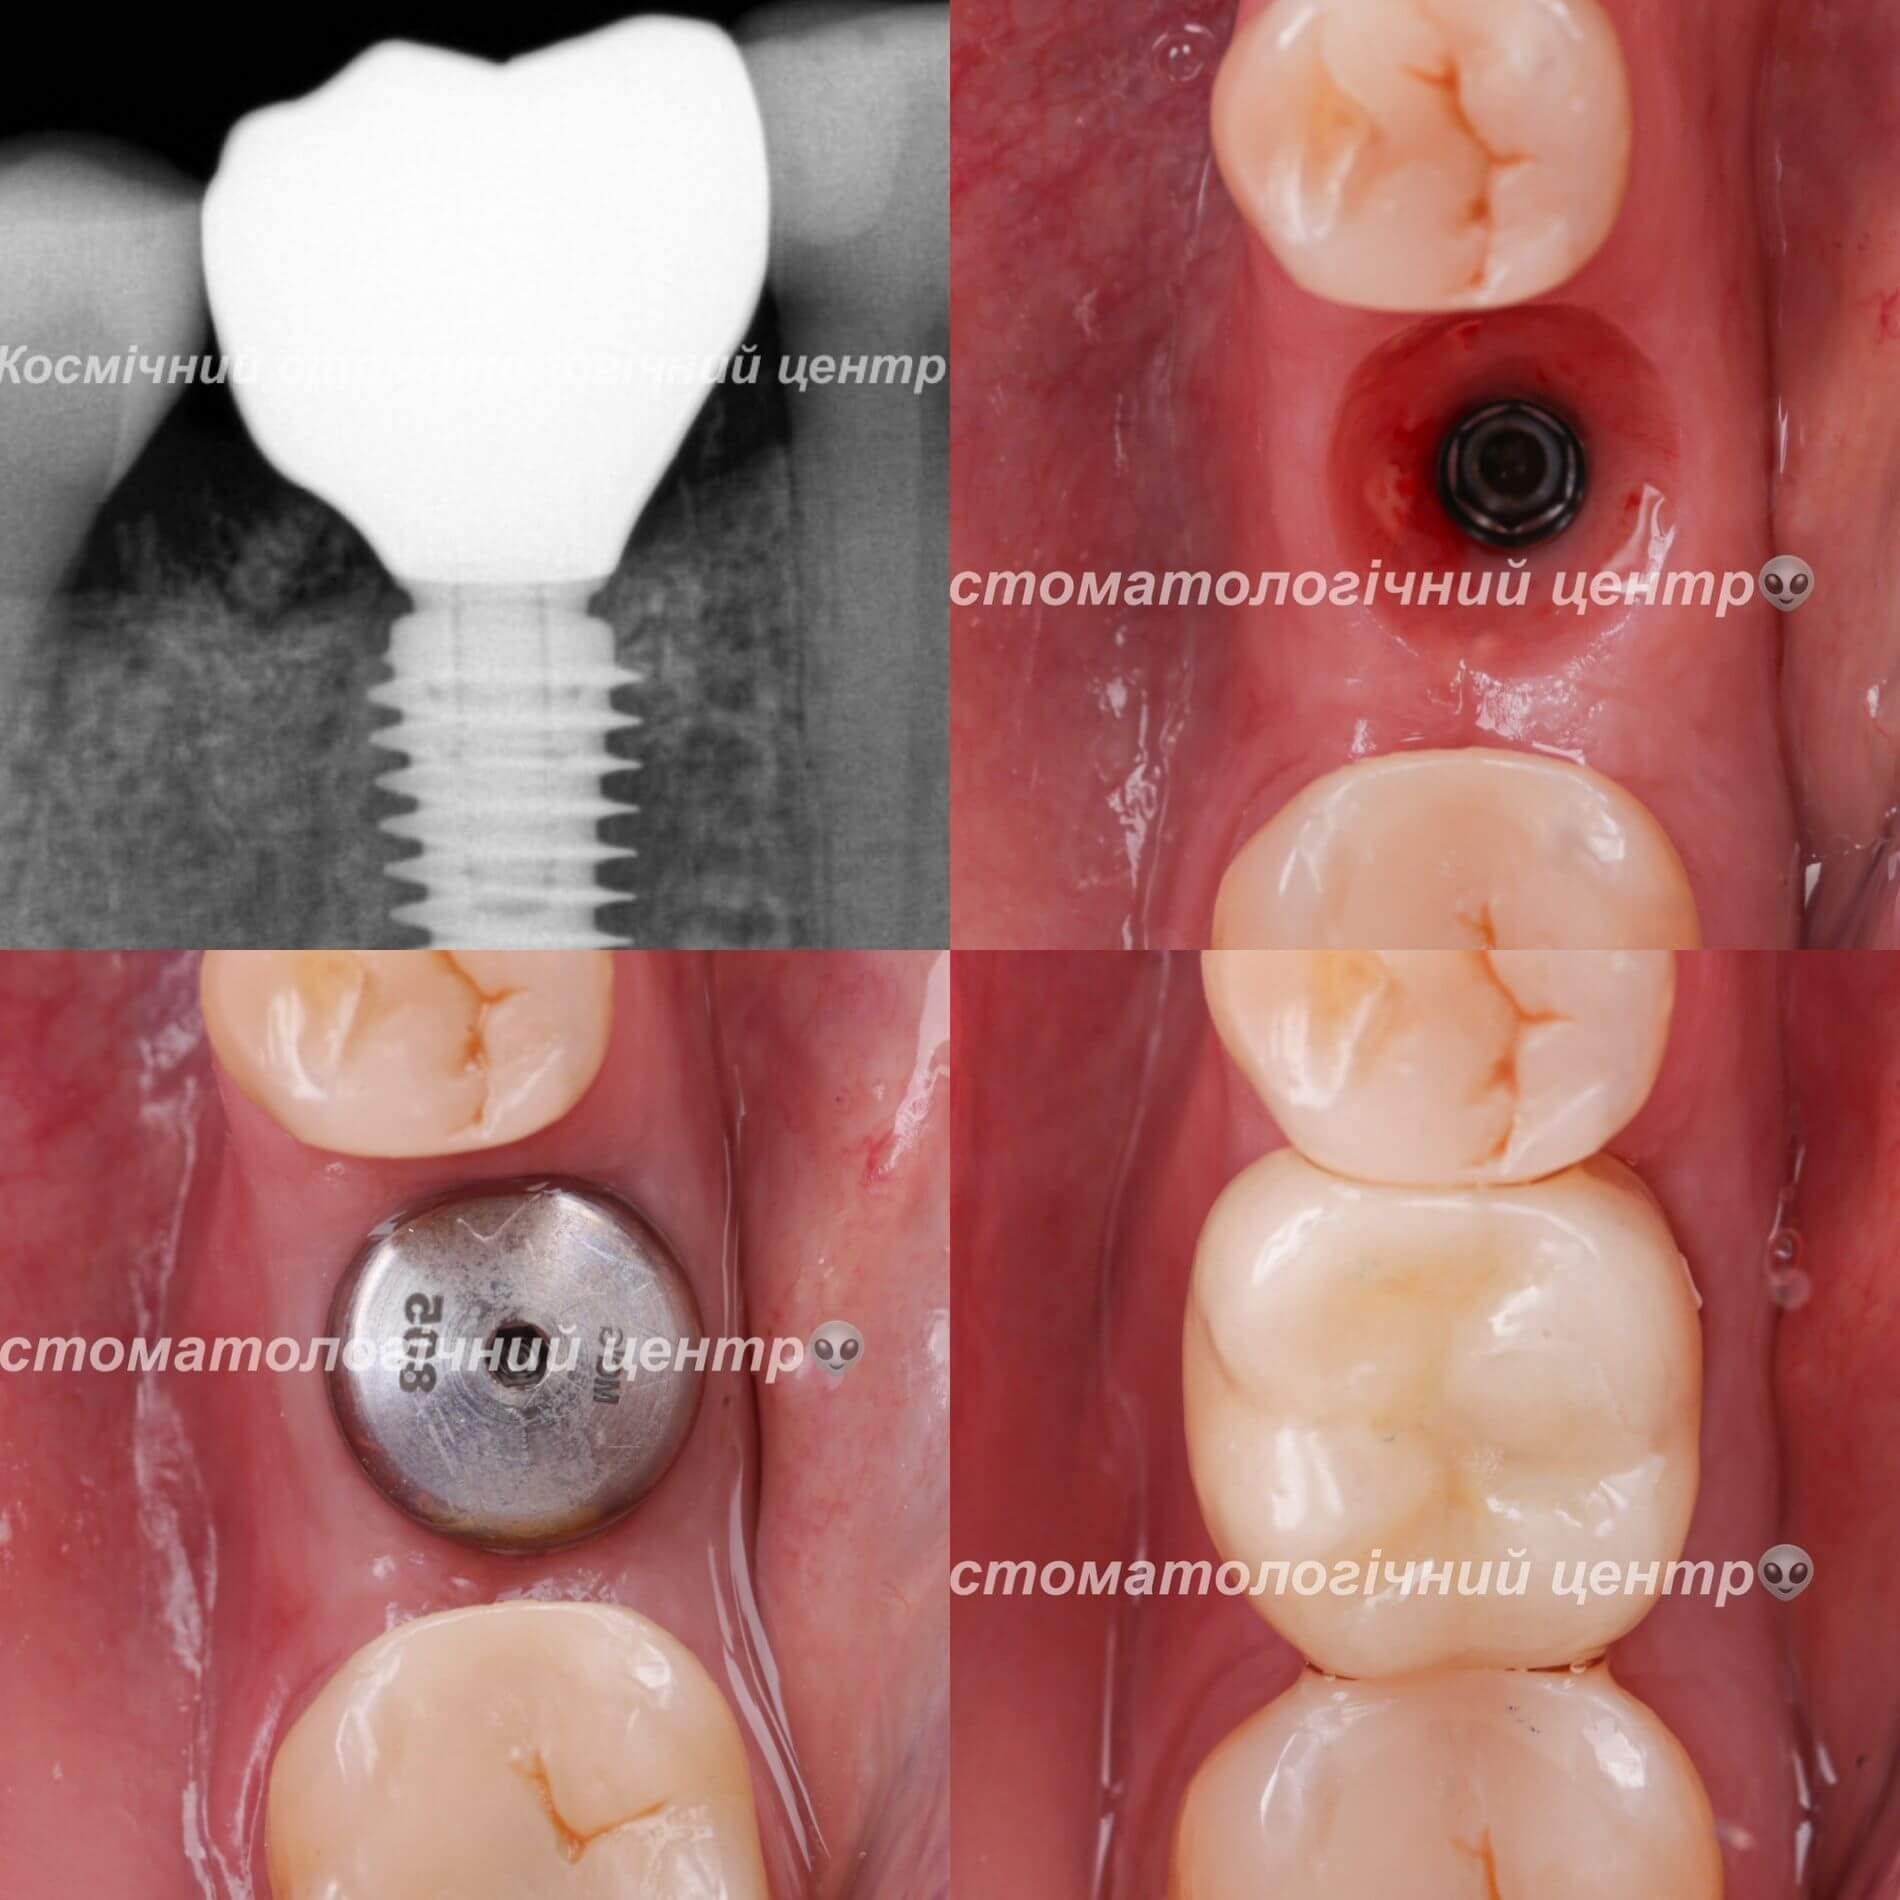

- Одноетапна імплантація відбувається за один візит, шляхом встановлення імпланту на місці видаленого зуба. Такий спосіб має свої обмеження: наявність достатнього для імплантації обсягу кістки та відсутність запальних процесів (наприклад, кісти). Коронка виготовляється одночасно з встановлення імпланту;

- Двоетапна імплантація відбувається в два послідовні етапи: спочатку здійснюється встановлення імпланту та витримується термін його повної остеоінтеграції (2-4 місяці, в залежності від щелепи), після чого встановлюється коронка;

Який з методів кращий? Однозначної відповіді нема. Але для оптимальної остеоінтеграції, двоетапна імплантація підходить краще, адже витриманий термін дозволяє досягти необхідного зчеплення між імплантом та кісткою щелепи.

- кріплення абатменту та коронки;